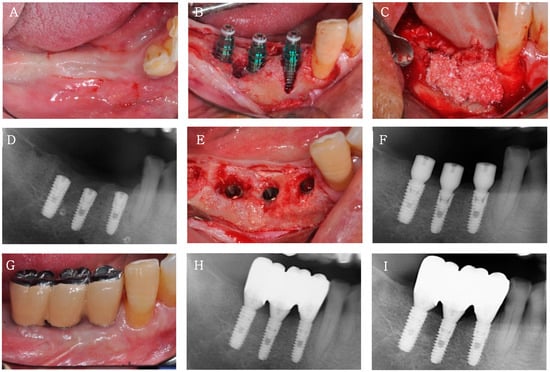

A 77 year old man visited the clinic for implant placement in the 44–46 region. After local anesthesia, when implants (TS III SA®, Osstem, Seoul, Korea) were inserted, one implant thread was partially exposed buccally. Therefore, the guided bone regeneration (GBR) procedure was performed on the peri-implant dehiscence defect using a mixture of Bontree® and whole blood, followed by adaptation of a collagen barrier membrane (Ossix Plus®, Datum Dental Biotech, Lod, Israel). During the second-stage implant surgery performed 4 months after implantation, sufficient horizontal bone augmentation was observed around the implants. The final prosthesis was inserted approximately 6 months after implantation (Figure 4).

Figure 4.

Clinical case 1. (A) Clinical view before bone augmentation and implantation of 44, 45, and 46. (B) Peri-implant dehiscence defects at 44 and 45. (C) Bone augmentation at 44 and 45 using Bontree® and collagen barrier membrane. (D) Radiograph after bone augmentation and implantation. (E) Clinical view after flap elevation during the second-stage implant surgery 4 months after implantation. (F) Radiograph after the second-stage implant surgery. (G,H) Clinical and radiographic views of the final prosthesis 6 months after implantation. (I) Radiograph at 1 year after loading.

A total of eight implants were placed in three patients who underwent sinus or alveolar ridge bone grafting with Bontree®. None of the patients had postoperative complications other than slight swelling at the surgical site. At 4 months after implantation, the ISQ values were >60 for all implants, indicating good implant stability (Table 1). All eight implants in all three patients were followed up for at least 12 months after functional loading, and the success rate, which was evaluated on the basis of the International Congress of Oral Implantologists Pisa Consensus implant health scale [], was 100% (Table 1). The radiograph at the 1 year follow-up showed integration of the implant with the regenerated bone and no bone loss or peri-implant radiolucency. No decrease in graft height was observed on any radiograph, and healthy peri-implant mucosa was established around all implants during the 1 year loading period.